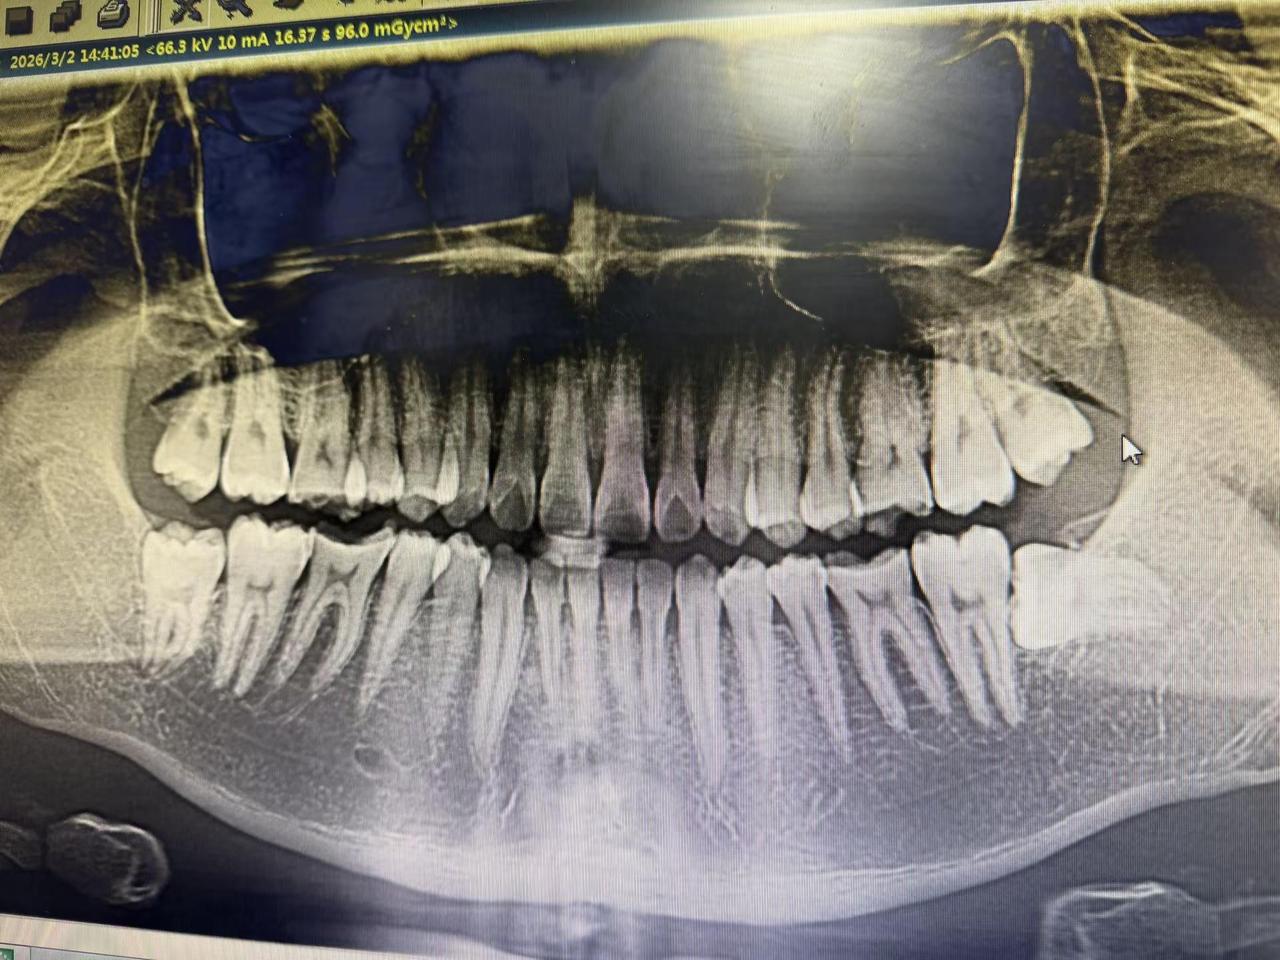

老铁们长智齿了。